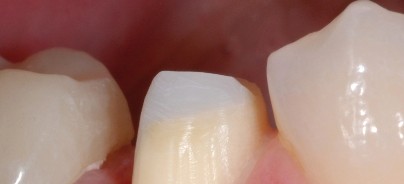

Die modernen Wurzelstiftsysteme – ob Quarzoder Glasfaserstifte – haben dagegen eine dem Dentin ähnliche Elastizität und lassen sich bei Bedarf einfacher wieder entfernen. Früher hieß es, jeder wurzelgefüllte Zahn muss überkront werden, das ist mit den direkten Stiftaufbauten in Adhäsivtechnik nicht mehr zwingend notwendig. Die Verwendung eines solchen Systems ermöglicht mir vor allem eine minimalinvasive Präparation im Wurzelkanal. Gleichzeitig habe ich einen elastischen Wurzelstift, der sich gut in der Länge bearbeiten lässt, und der ästhetisch ist, weil er gerade im Frontzahnbereich keine Schatten wirft und es zu keiner dunklen Verfärbung an der marginalen Gingiva kommt.

Bei mehreren Wurzeln ist es für den klinischen Langzeiterfolg entscheidend, nicht auf Länge zu gehen, sondern den Stift im oberen Drittel zu verankern bzw. lieber alle Wurzelkanäle zu versorgen und divergierend zu verankern. Die sehr kleinen Durchmesser der transluzenten Fiber Posts von 0,8 bis 1,6 mm erleichtern mir hier eine gute Verankerungsmöglichkeit. Dadurch, dass ich so in verschiedene Richtungen Stifte stehen habe, erhalte ich insgesamt eine recht gute Stabilität.